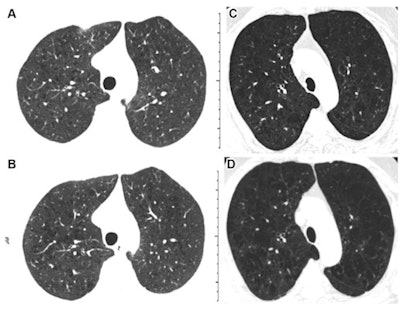

"Using a previously validated computer algorithm for automatic grading of emphysema pattern according to the Fleischner Society criteria, we demonstrated that an increase in emphysema grade on sequential CT scans is associated with substantial disease progression and increased risk of mortality," the group noted.

To this end, they conducted an analysis that included 5,056 participants in the Genetic Epidemiology of Chronic Obstructive Pulmonary Disease (COPDGene) study who were current and former smokers and had undergone baseline and follow-up CT scans between 2007 and 2017. The presence of emphysema on CT was measured at the initial exams by the Fleischner grading system (which ranges from 0, or absent, to 5, or "advanced destructive") and at five-year follow-up exams by a deep-learning model developed and validated with Python and PyTorch.

Of the total cohort, 26% had Fleischner emphysema scores that had increased by one or more categories at five-year follow-up, progression which manifested in more airflow obstruction and shortness of breath compared with baseline assessment, shorter six-minute walk distances, greater extent of disease, and lower quality of life. (Increased Fleischner emphysema grade on follow-up is associated with a higher mortality rate, the team noted.)